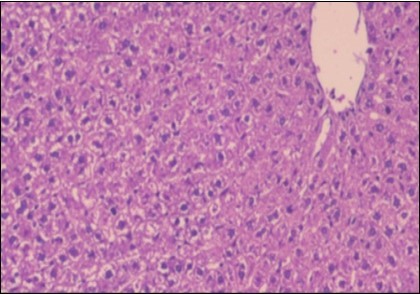

Effect of Ator, Fennel and Their Combination on the Liver of Obese Rats

The histological examination of the livers of control rats feeding standard diet showed normal architecture hepatocytes, blood sinusoid and central vein, figure 6. The rats which were fed on a (HFD), showed swollen hepatocytes with vacuolated cytoplasm filled with fatty infiltration, congested central vein and disappearance of blood sinusoids, figure 7. By comparison, the liver of rats that were treated by fennel after obesity and control mice observed nearly normal of the hepatocytes with eosinophilic cytoplasm, central vein and clear blood sinusoids and more bi-nucleated cells, figure 8. While examination of rats' liver that were treated by Ator and after the obesity appears, they showed mild fatty change in hepatocytes, few hepatocytes retain is eosinophilic cytoplasm and central vein figure 9. Liver of rats that were treated by fennel and Ator after obesity and control rats are showing nearly normal hepatocytes figure 10.

Figure 6.Photomicrogragh of liver section of control rat showing normal architecture Hepatocytes, blood sinusoid and central vein, (H&E) (40X).

Figure 7.Photomicrograph of liver section of obese rat showing swollen hepatocytes with vacuolated cytoplasm filled with fatty infiltration, congested central vein and disappearance of blood sinusoids, (H&E) (40X).

Figure 8.Photomicrograph of liver section of treated rat with fennel herb showing nearly normal of the hepatocytes with eosinophilic cytoplasm, central vein (CV) and clear blood sinusoids and more bi-nucleated cells , (H&E) (40X).

Figure 9.Photomicrogragh of liver section of treated rat with Ator drug showing mild fatty change in hepatocytes, few hepatocytes retain is eosinophilic cytoplasm and central vein , (H&E) (40X).

Figure 10.Photomicrograph of liver section of treated rat both with both fennel herb and Ator drug showing nearly normal hepatocytes (H&E) (40X).